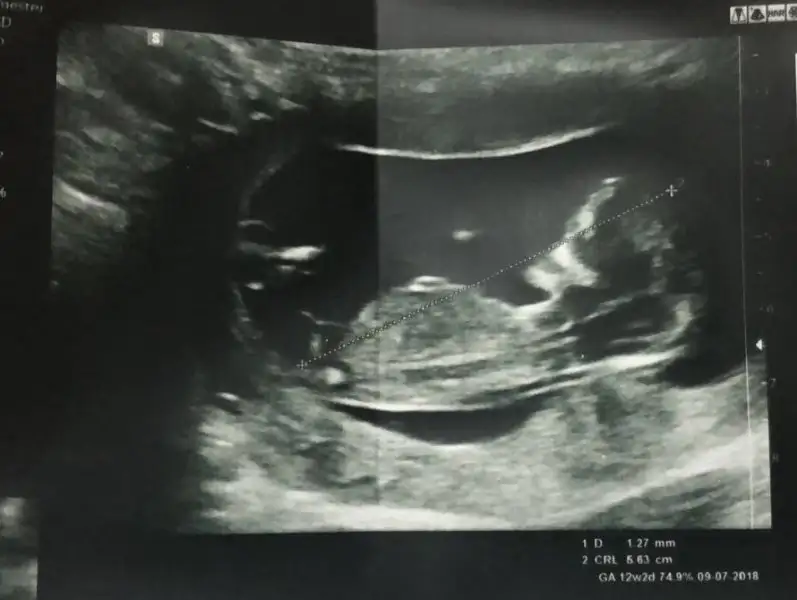

Merhaba, ultrason görüntülerinde sat'a göre 11+4 üz.

cinsiyet tahmini yapabilecek olan var mı:)

IMG_4481.webp IMG_4475.webp IMG_4476.webp IMG_4483.webp